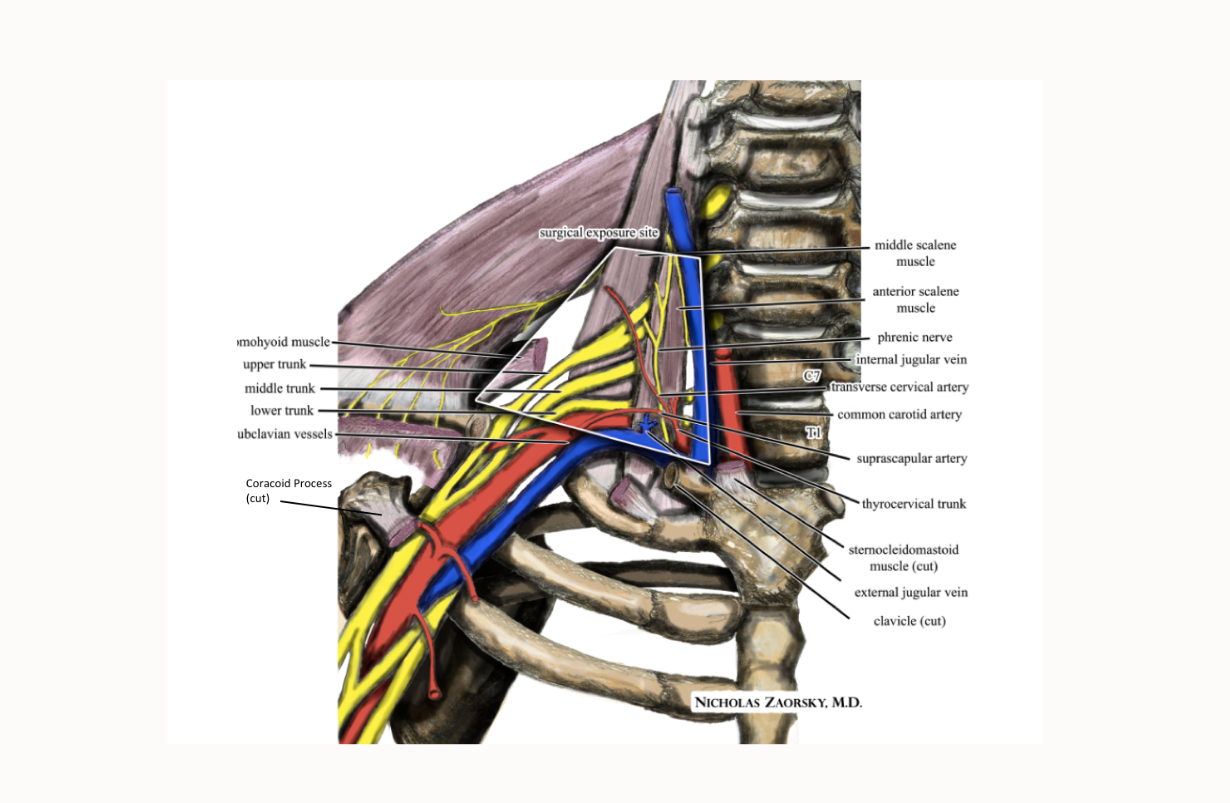

Thoracic Outlet Syndrome

Thoracic outlet syndrome occurs when nerves and/or blood vessels that serve the arm are compressed in the upper chest before entering the arm. The nervous elements, the brachial plexus, are the more common cause of arm and hand tingling, positionally related weakness, and pain; the vascular elements are subclavian and axillary. Usually the symptoms occur in certain positions, such as raising the arm overhead or depressing the shoulder. Medical treatment involves botulinum toxin to relax the scalenus muscles. BENEFICIAL POSES: Bharadvajasana II, Parighasana, Vrksasana, Garudasana,. EXPLANATION: The brachial plexus descends from the cervical spine between the scalenus anticus and medius muscles. Bharadvajasana II and Parighasana stretch these muscles, giving the nerves more slack to get out of harm's way between the clavicle and the coracoid process , two boney elements which they pass under as they enter and exit the thorax. Vriksasana and Garudasana aid in improving humeral control and scapular (shoulder blade) kinetics, both of which help people avoid the nerve compression that causes this syndrome. REFERENCE: Watson LA, Pizzari T, Balster S. Thoracic outlet syndrome part 2: conservative management of thoracic outlet.Man Ther. 2010 Aug;15(4):305-14. doi: 10.1016/j.math.2010.03.002. Epub 2010 Apr 9.